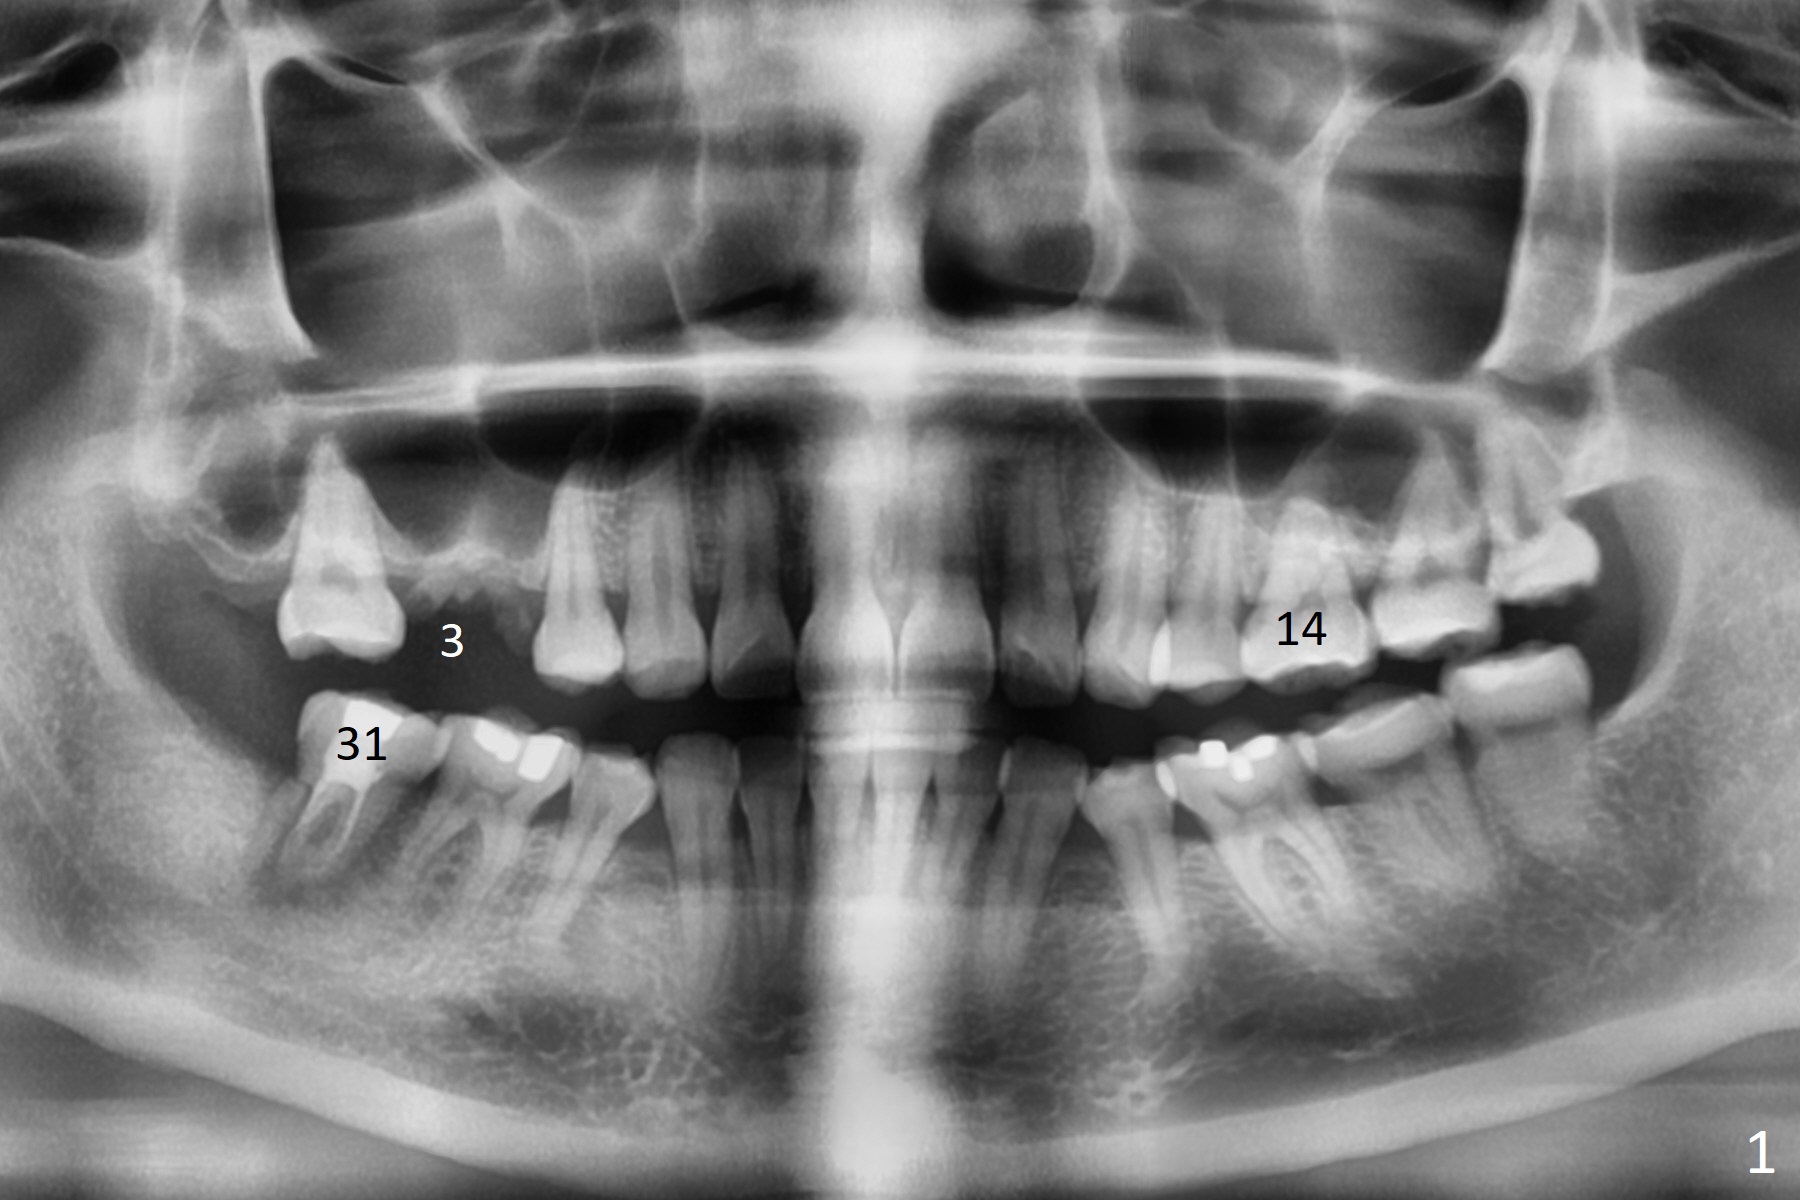

A 36-year-old woman is nervous about dentistry. She will take Valium by herselft before surgery (Fig.1). The tooth #3 has 3 residual roots (Fig.2 (CBCT 3 D occlusal view)). The bone is 2-3 mm thick (Fig.3,4 (sagittal, coronal sections)). A 5x7.3 mm implant will be placed with IS guide (Fig.5 (12 mm offset)). Since IBS implants are able to achieve amazing stability in the thin bone, prepare the shortest 4-5 mm in diameter dummy implants (IS (better surface treatment) and IBS) after sinus lift using UF Guided Sinus Lift Approach Kit (surgery). With intact tooth structure at #14, the bone height is not much (Fig.6), congenital (genetic) in nature. The infection at #31 is more severe (Fig.7). Extraction will be the 2nd in order. Because of limited bone, it is better to do bone graft first. The patient is concerned about the discolored upper right canine, which should be associated with orthodontics 20 years ago (take photos). The apical canal is obliterated (Fig.8,9 arrow) with periapical radiolucency (arrowhead). In fact the bone at #31 is so little that the tooth will be extracted for socket preservation.